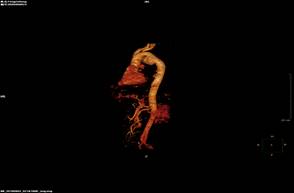

患者头昏乏力、心悸1月,患骨髓增殖性疾病已有6年,入住我院血液内科,检查表示重度贫血。胸部增强CT发现主动脉弓局部明显膨大并瘤样外凸,考虑胸主动脉瘤,大小约3cm×4cm,经心胸外科医生会诊,转入心胸外科,在完善CTA检查后,提示胸主动脉夹层动脉瘤形成,随时存在破裂风险,严重威胁患者生命。

患者的病情就是命令,在紧急情况之下,为保患者生命无忧,心胸外科副主任母存富立即协调相关科室,由血管外科硕士王贤芝医师、心胸外科团队成员在局麻、DSA造影下行“胸主动脉夹层动脉瘤腔内修复术”,参与此次手术的还有麻醉科王义主任、王莉副主任医师,心内科胡永奎副主任医师,介入科李江涛主任、杨华护士长等医护人员。手术过程十分顺利,造影提示瘤体完全封闭、支架无内漏,股动脉穿刺点无渗血。术后患者生命体征平稳,病情恢复良好。